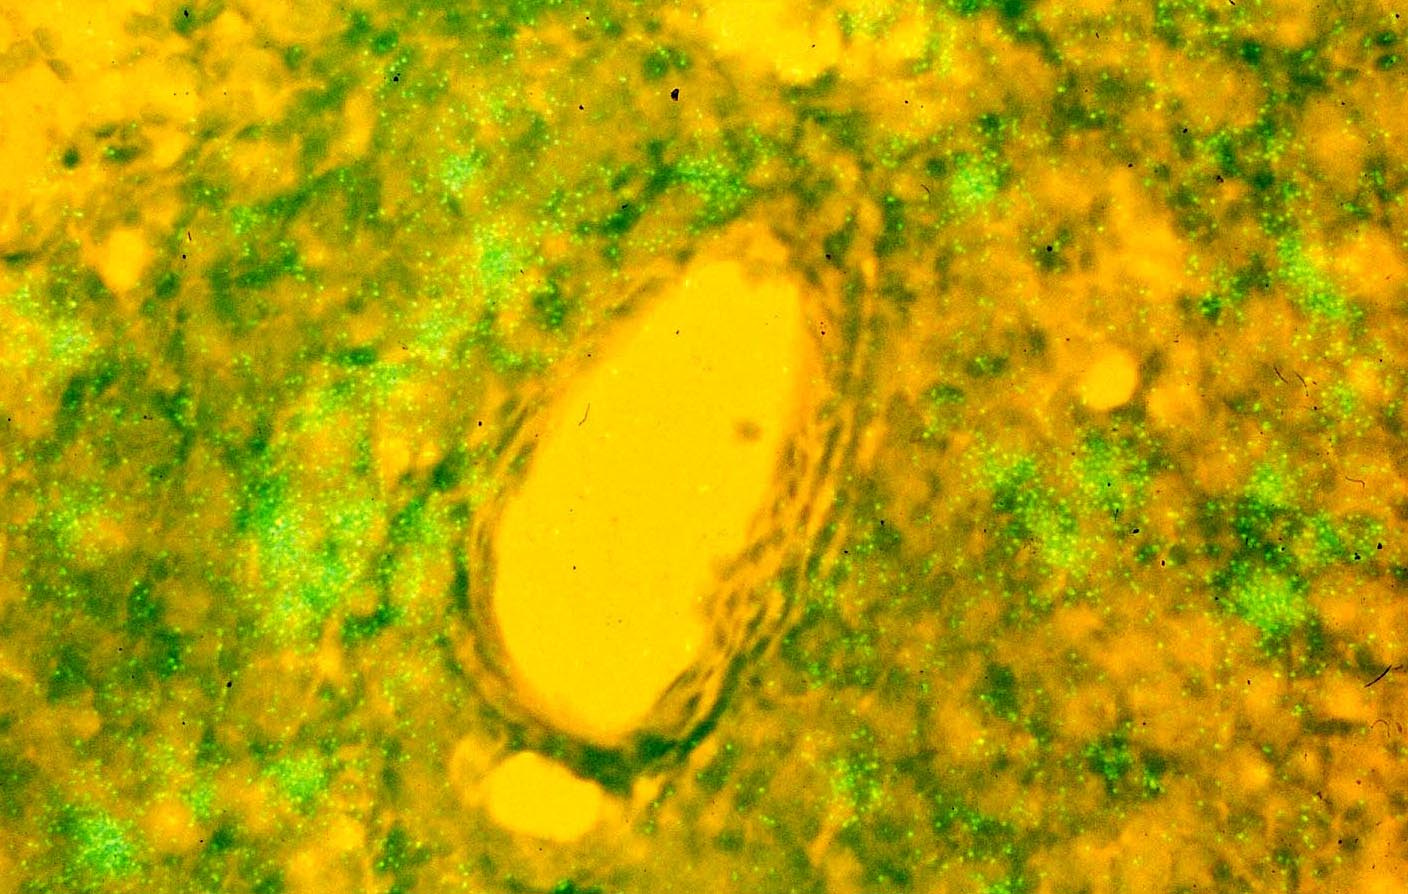

HIV DNA (green nuclei) detected by in situ PCR in CD4+ T cells around a blood vessel (Ashley Haase)

In the early 1990s, it was discovered that HIV infection is both active, replicating continuously, and latent, creating reservoirs in lymphatic tissues. Ashley Haase and colleagues made the latter discovery, publishing their findings in 1993. In his post, Ashley describes the exact moment of discovery and how researchers are still asking important questions 25 years later. The complexity of viral reservoirs, and the obstacle this creates in finding a cure for HIV, is also discussed in a post by Joseph Wong.